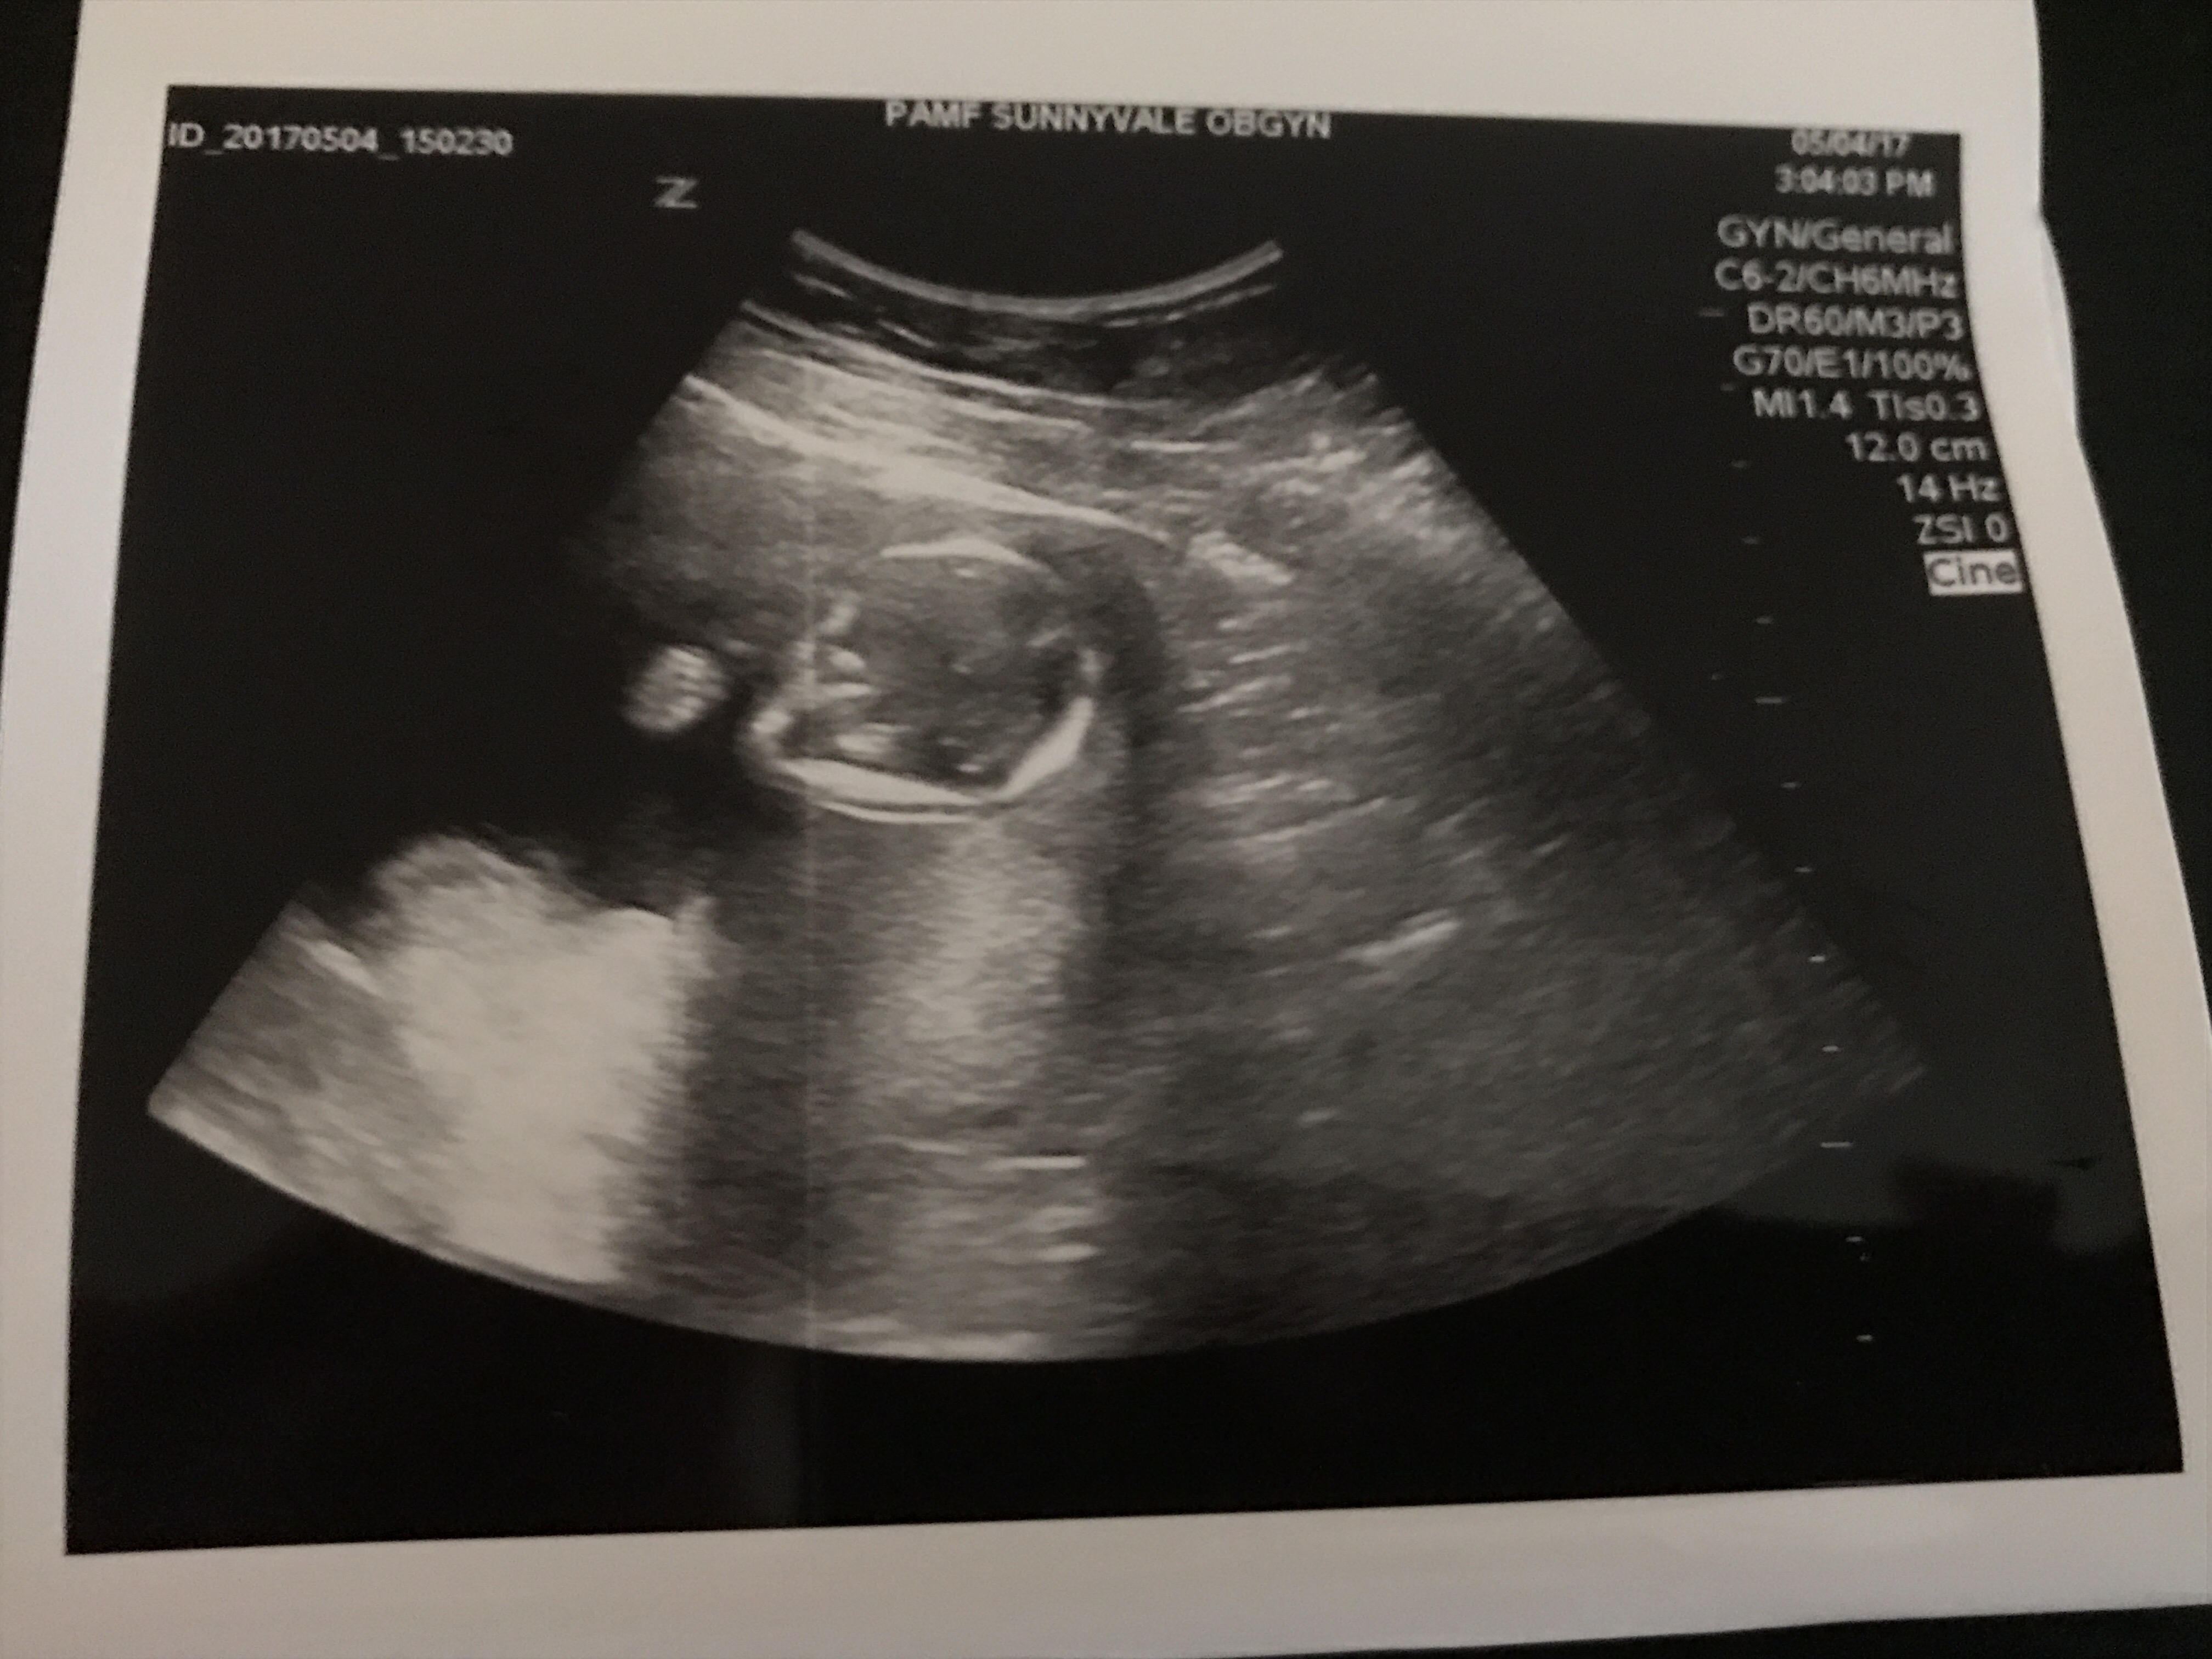

As usual getting an ultrasound was one of the highlights of our visit. I made sure to ask Dr. G if I would be able to tell the gender from these and had a sleep mask I was prepared to wear so as to not see inadvertently if that was the case, but he assured me these would not give it away, so I was able to look and take some photos home with me. At one point baby made a fist for us, I’m not sure if it is in one of these photos, but if it is my guess is it is in this one below.

Dr. G. pointed out some of baby’s features to us that he had not before including his or her spine. I remarked that it look good to me, and he agreed that it looked good to him also. It’s so amazing to get to see these great peeks at our developing baby, even if it’s hard to figure out what a lot of the photos are, in fact I have a few from him that I can’t make out much of anything from in addition to the great detailed ones I’m posting.